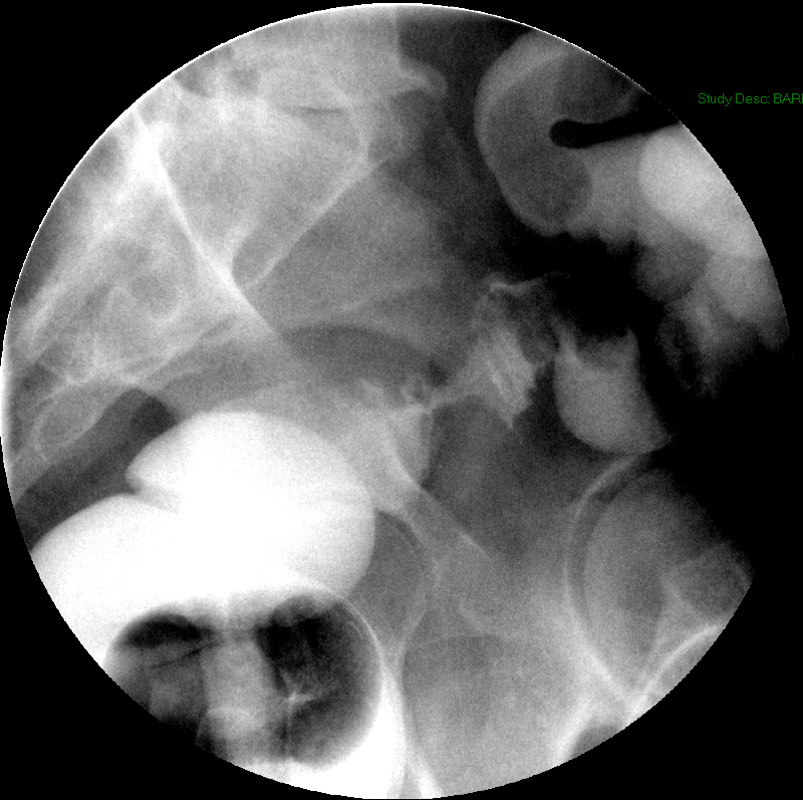

- Have the patient move into the right anterior oblique position.

- Slide a compression paddle under the patient (balloon deflated) so that it is positioned on the duodenal bulb.

- There is a radiopaque ring on the paddle that will help you determine the center of the paddle.

- Inflate the bulb on the compression paddle and obtain single contrast compression spot films of the duodenal bulb and the C loop

(key image 14)

(key image 15)

(key image 16)

(key image 17)

(key image 18).